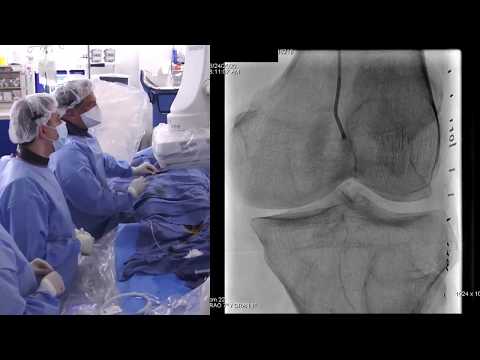

Live Case: Complex SFA CTO and BTK Treatment